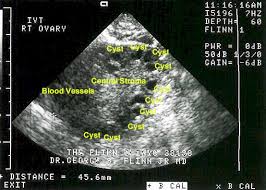

In these women the ovaries appear polycystic so characterized by an increase in antral follicles and ovarian stroma as well as by theca cell hyperplasia and ovarian cortical thickening.